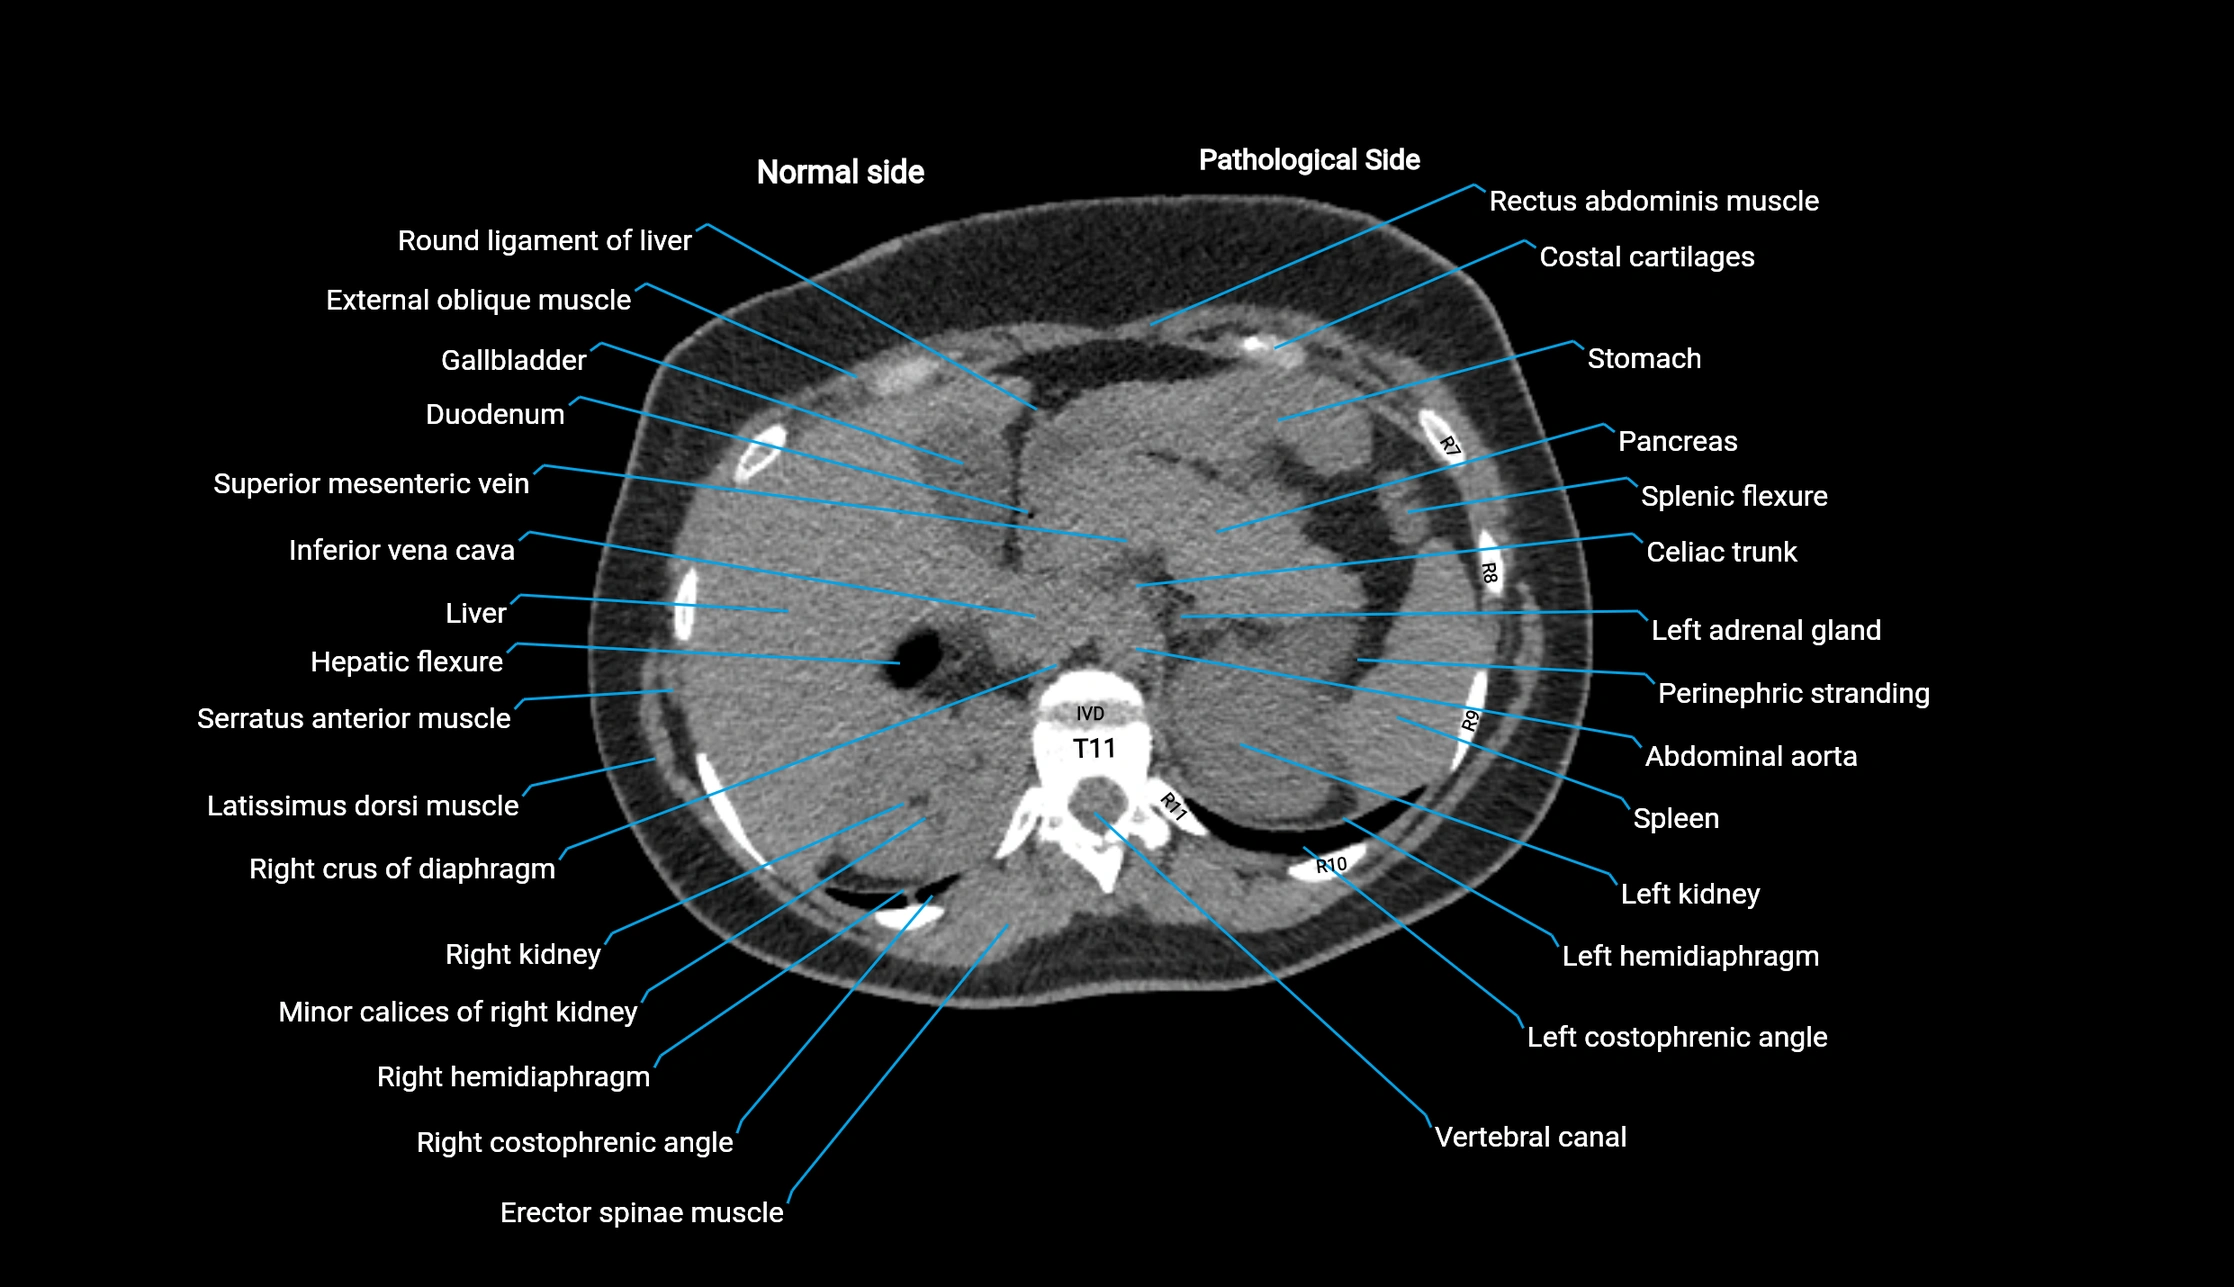

CT image

image